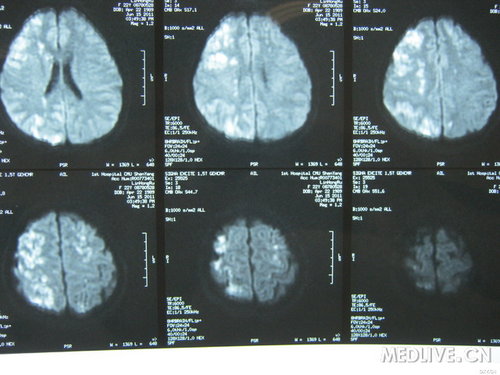

病史特点:22岁年轻女性,以“头痛伴右眼视力下降,左侧肢体活动不灵2天”为主诉入院,2天前在美容院行额头填充物--玻尿酸取出手术时突然起病,自觉全身发热不适,呼吸急促,并出现抽搐发作:双眼向右侧凝视,双上肢屈曲,右腿伸直,左腿屈曲,呼之不应,无尿失禁及舌咬伤,5-6分钟缓解。抽搐后1小时患者开始出现右眼视物不清,右侧后枕部严重疼痛伴恶心呕吐,且左侧肢体麻木,急送医院,行头CT无异常,但出现左侧肢体不能活动,且频繁呕吐,转我院就诊,行头MRI+DWI检查提示:右侧大脑半球,侧脑室旁,半卵圆中心及左侧额叶皮呈及皮呈下多发长T2信号,DWI高信号。

检查:头MRI+DWI:描述如上,急性脑栓塞?

DWI像

病例特点:青年女性,发病时有癫痫发作,其后出现左侧肢体运动障碍,并右眼视力下降。脑MR可见颅内广泛病变,以左侧脑白质为主。